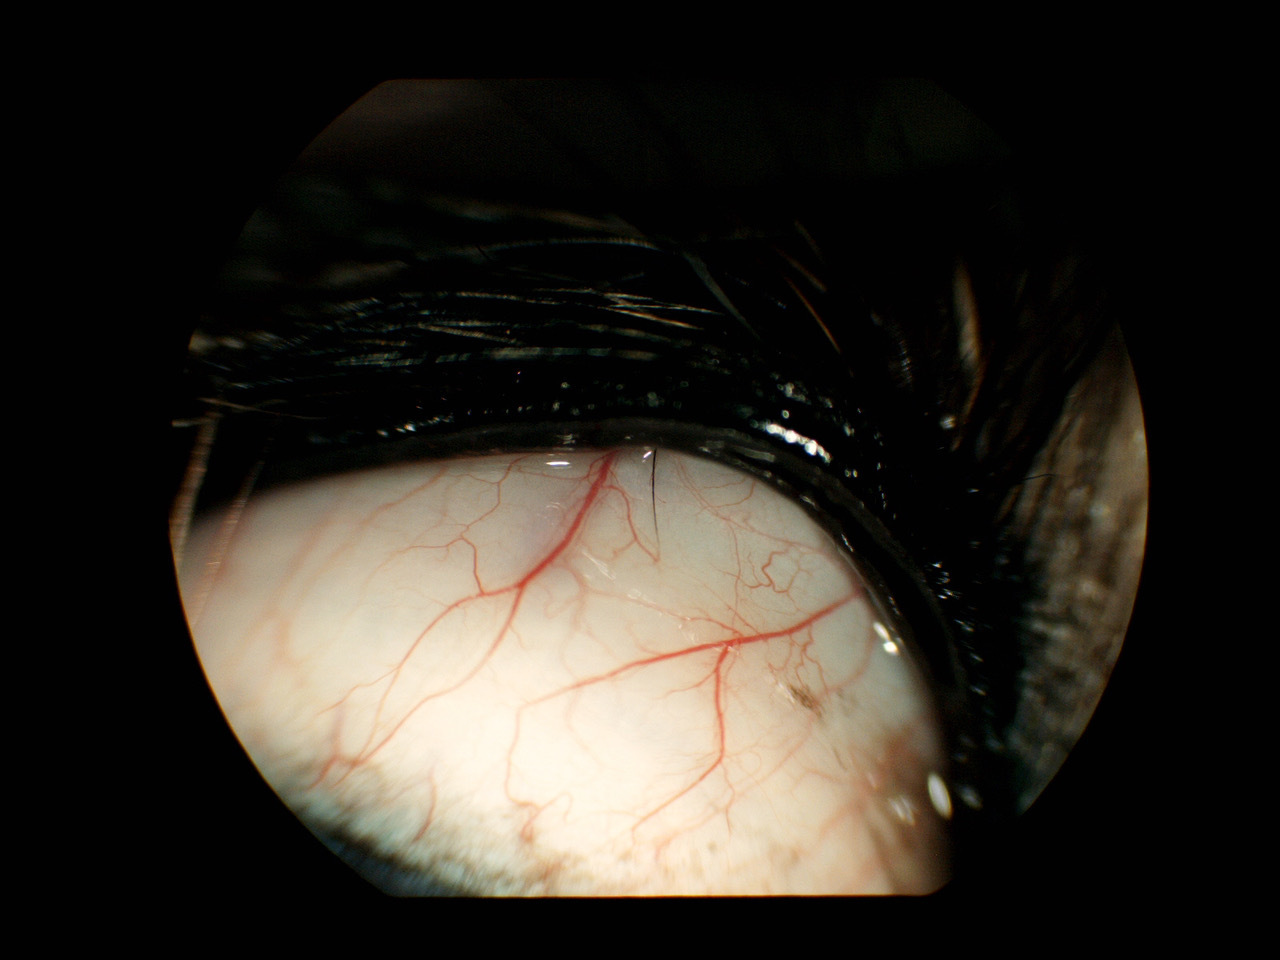

Diese Wimpern sind nicht so leicht zu erkennen. Da der Hund mit dieser Problematik sehr schmerzempfindlich am Auge ist, muss dieses erst mit einem lokalen Anästhetikum betäubt werden. Dann dreht man das Lid nach außen um, um auf die Innenfläche sehen zu können. Auch hier benötigt man eine Lupenvergrößerung, es empfiehlt sich eine „Spaltlampe“, die eine 10-16-fache Vergrößerung bietet. Ebenfalls können diese Härchen bei ruhigem Hund und ruhiger Hand manuell entfernt werde - jedoch wachsen sie wieder nach. Lulu hatte an beiden Oberlidern mehrere Stellen, an denen einzelne Haare und auch kleine Haarbüschel aus der Bindehaut austraten.

Die Methode der Wahl ist die operative Entfernung der gesamten Haaranlage. Dazu wird der Hund in Vollnarkose gelegt. Mit einer speziellen runden Klammer wird das Lid gefasst und zur Verminderung der Durchblutung leicht abgeklemmt und nach außen gedreht. Das im Zentrum befindliche Haar, bzw. der Haarbüschel wird dann mit einer Skalpellklinge blockartig mit der gesamten Haaranlage herausgeschnitten. Eine Naht ist nicht nötig. Die Nachbehandlung erfolgt mit einer antibiotischen Augensalbe über mehrere Tage.